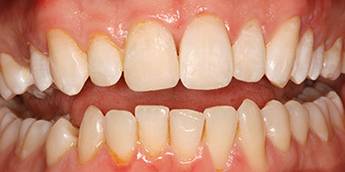

10. eset

Savas kémhatású anyagok, mint például a szénsavas üdítők túlzott használata is a fogak zománcrétegének nagyfokú károsodását okozhatják. 35 éves férfi páciensnek készítettünk a frontfogaira Zirkon koronákat, a rágófogaira pedig fémkerámia szóló koronákat. 28 koronával állítottuk helyre a fogazatot.